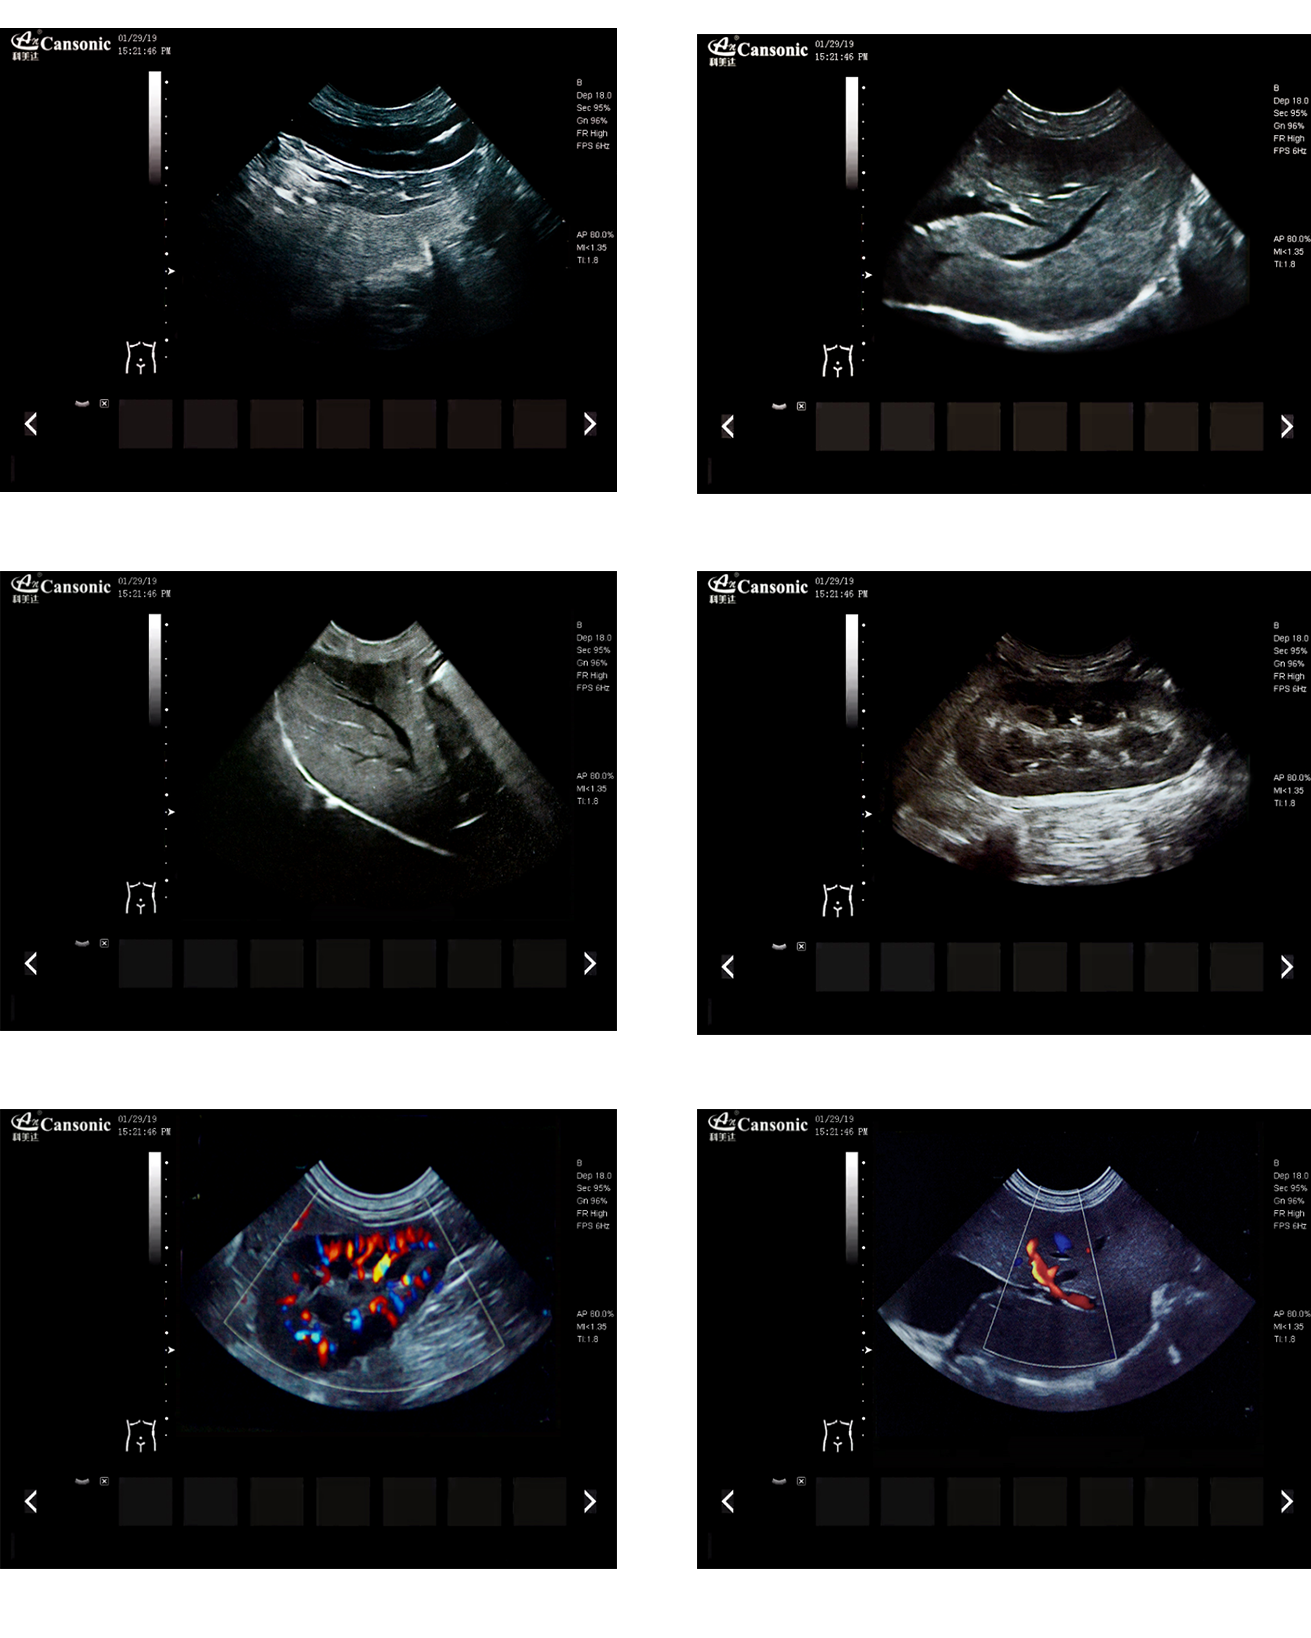

K2V

1、薈萃前沿成像技術(shù),實(shí)現(xiàn)高精與靈便的完美融合,提供完整的動物彩超診療方案

2、專業(yè)的獸用測量軟件,簡捷的工作流,適合犬、貓、馬、牛、羊等 各類大小動物

3、iClear斑點(diǎn)噪聲抑制抑制噪聲干擾,使動物組織結(jié)構(gòu)更清晰

4、具有廣泛的動態(tài)范圍,顯示出色的組織均勻性,減少了偽影及噪聲

5、精細(xì)血流識別技術(shù),增加了可疑病變更多的信息分析

6、先進(jìn)的算法帶來清晰的穿刺針顯示,降低穿刺活檢操作難度

7、圖像優(yōu)異,同時性能穩(wěn)定,每天能進(jìn)行大量的動物超聲檢查

8、輕巧的機(jī)身,耐摩損的把手,適應(yīng)各種復(fù)雜的動物使用環(huán)境

臨床圖示